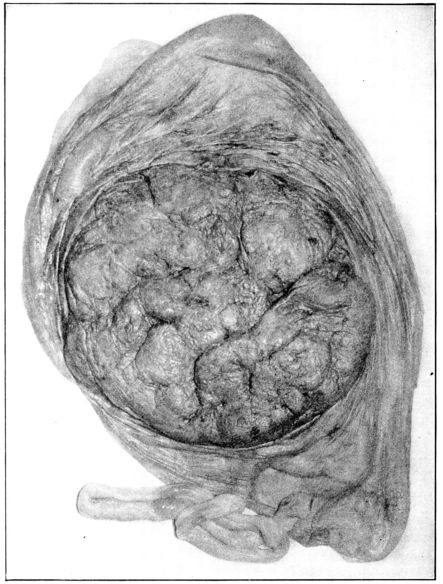

22. Photograph of placental vessels 72

23. Maternal surface of the placenta 74